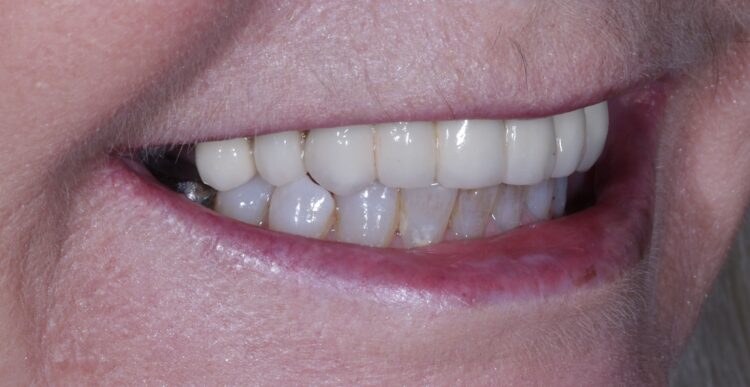

Dr Omar Iqbal replaces a patient’s failing bridge in the aesthetic zone with a new prosthesis fixed in place with two Tapered Pro Conical implants.

The patient returned to the practice for review two weeks post-surgery and to confirm successful and otherwise uneventful healing. Discomfort was minimal and she reported being very satisfied with the outcome. After a healing period of three months, the patient returned to begin making the final prosthesis. Good soft tissue adaptation was noted around the temporary prosthesis and the buccal contour was successfully maintained.

Upon professional reflection, this case went according to plan, emphasising the importance of meticulous assessment and preparation prior to implant surgery. The guided approach helped to ensure the precise positioning of the implants which facilitated connecting the temporary bridge. This, alongside the implant selection, was crucial for maximising on the limited bone available for primary stability.

The Tapered Pro Conical implant from BioHorizons Camlog is a game-changer, offering a new narrow diameter option for enhanced versatility in areas with limited bone. Its conical connection improves the implant-prosthetic interface and emergence profile, delivering optimal aesthetics, while the titanium alloy (Ti-6AL-4V ELI) delivers exceptional strength. It is indicated for use in the mandible and maxilla, single tooth replacements, fixed bridgework, and overdentures. With high insertion torque limits of up to 136 Ncm, the Tapered Pro Conical implant also ensures stability and success in a range of clinical scenarios.